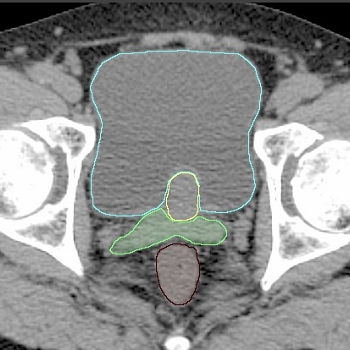

Contouringの例

治療計画CT

前立腺

・前立腺周囲には、静脈叢、深陰茎背静脈の浅枝、肛門挙筋などがあり、単純CT上では区別は難しいことも多いため、不用意に大きく囲まないよう注意が必要である。

・apexは、前立腺癌の好発部位のひとつであり、contouring時に注意が必要である。MRIの冠状断にて、penile bulbからのGU diaphragmの厚さまたはApexまでの距離を測定しておき、CTでのcontouringでの確認に利用する方法もある(図1)。また、再構成した矢状断で、大まかなpenile bulbやGU diaphragmの位置から推定する方法もある(図2)。

・前立腺を囲んだ後、矢状断、冠状断または3Dで表示させてみて、形がいびつでないか、不自然な凹凸がないか、penile bulbやGU diaphragmとの位置関係などを確認する。

・囲んだ前立腺の体積を計算し、USでの結果等と比較する。

(図1)CTでは、Apexと尿道を区別することは難しく、MRIにてPenile bulbからの GU diaphragmの厚さまたはApexまでの距離を測定し、CTVのcontouringに反映させるとわかりやすい。ApexのどこまでをCTVに含めるかについては、腫瘍の好発部位であるapexを十分含める(左図のように1-2スライス多めに含める)という考え方と、MRIで判断されるapexまでに限定してCTVとするという考え方がある。

直腸

本試験では、直腸は、肛門(座骨結節のレベル)から直腸S状結腸移行部まで(通常、仙腸関節の尾側端以下のレベルとなる)、充実性の臓器として囲む。欧米での臨床試験ではこの囲み方で直腸線量が評価されていることが多く、過去の他施設の報告とも比較しやすい (1)。

膀胱

膀胱は、膀胱頚部から底部まで、筋層を含めて充実性の臓器として囲む。

標的体積

GTV:前立腺(T3aの場合には、被膜外浸潤も含む)とする。

CTV:一般的には、低リスクの場合にはGTVのみ、中リスクの場合にはGTVおよび精嚢基部1 cm程度、高リスクの場合にはGTV+精嚢2 cm程度とすることが多い (2)。本試験では、高リスクに関しては比較的リスクの低いものに限定しているため、CTVは中リスク、高リスクともに、GTVおよび精嚢基部1 cm程度とする。

PTV:上記のCTVに患者固定再現性等を見込んだ適切なマージンを加える。本試験では前立腺合わせによるIGRTを行うため、CTVに4 mm(直腸側以外は最低5mm) ~8mmのマージンをつけると規定している。特に頭尾方向に関しては、CTスライス幅を考慮し、5~8 mm 程度のマージンを設定する。